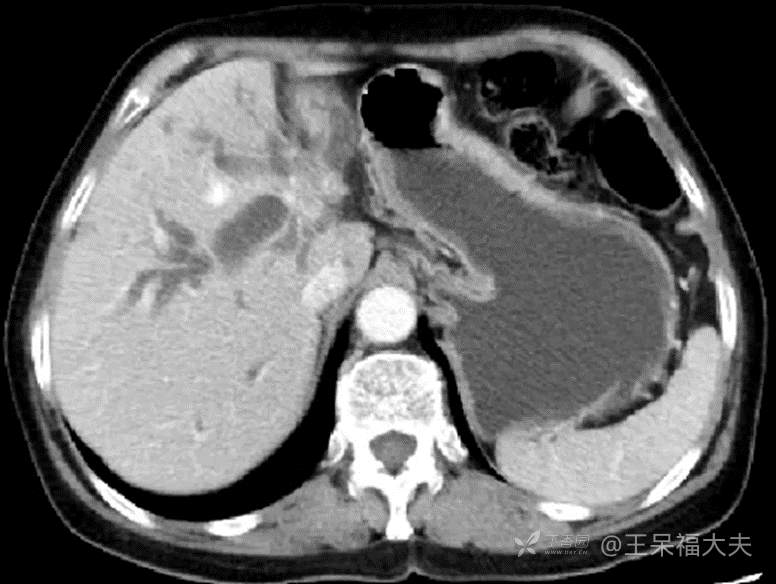

患者72岁女性,无明显诱因下出现皮肤巩膜黄染3周,当地检查提示“肝门部胆管癌”1周入院。既往体健,查体除皮肤巩膜重黄染无特殊。影像检查提示肝内外胆管扩张,门脉左支闭塞,右肝动脉根部受侵,如图:

图1:我看着像ICC侵犯肝门,也有人赌肝门胆管癌侵犯肝实质,结果我赢了一顿酒。